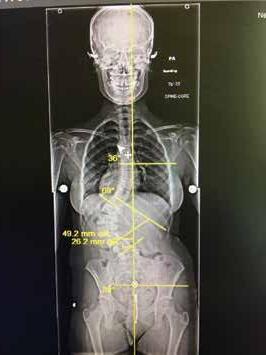

Total disc replacement (TDR) may be an alternative to spinal fusion for patients with cervical or lumbar herniated discs or degenerative disc disease.

The goals of total disc replacement surgery are to maintain segmental spinal motion, relieve pain, increase activity, restore disc height and proper spine curvature, and reduce post-operative recuperation time.

If you are experiencing neck or back pain and are considering surgery, isn't it worth your time to schedule an appointment with Dr. Jason E. Garber to nd out if motion preservation technology is an option for you?

Dr. Garber is one of Southern Nevada's most experienced spinal surgeons and a leader in arti cial disc replacement surgery.